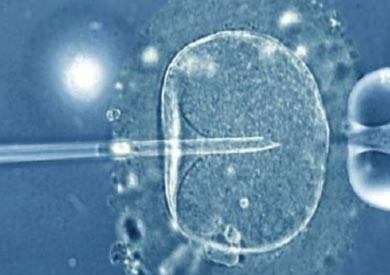

يحتاج إجراء هذه التقنية إلى ثلاثة أشخاص: زوج وزوجة وامرأة ثانية متبرعة. ويمنح الزوج نطفته (الحيوان المنوي: الخلية الذكرية)، ويؤخذ من الزوجة بُييضة تجرد من ميتاكوندياتها عن آخرها للتخلص من عوامل الإصابة المرضية المميتة المحتملة، وتستبدل بميتاكونديات سليمة تنتزع من بُييضة امرأة أخرى تظل مجهولة؟؟. أي أن المادة الحية للبويضة الملقحة جمعت من ثلاث مصادر. وما يلاحظ عن هذه التقنية التي رمت إلى إصلاح خلل يقع مقره في الهيولى “السيتوبلازما” أنها لم تكن تجد الطريق ميسرا وسهلا لو كانت هذا الفساد لصيقا بعناصر النواة Le noyau؟؟.